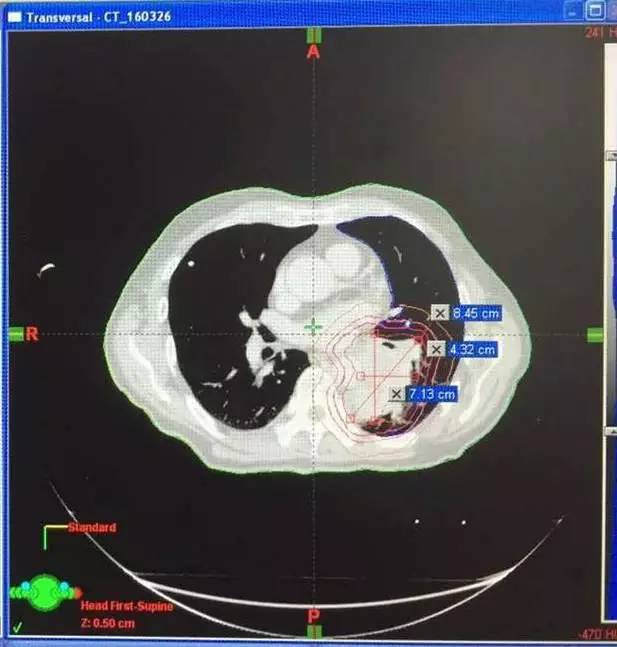

2016年3月,王先生因咳嗽加重就诊于当地医院,支气管镜病理检查提示:考虑小细胞癌的可能性大。

化疗一周期,病情无改善症状加重。

2016年4月,王先生接受了A45治疗,一个月后复查,病灶明显缩小,2016年7月复查,病灶进一步缩小,由于A45治疗具有明显的远观效应,能够激发自身的免疫系统,长期有效的消灭体内肿瘤,2016年12月,王先生肺部病灶几乎全部消失。

治疗前

治疗后

治疗后两个月

治疗后7个月

目前王先生状态良好,没有任何复发迹象。